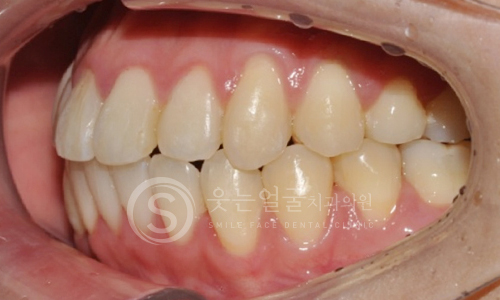

한눈에 보는

임플란트 전후사진

환자 개개인의 치아 형태와 구강 구조에 맞춘 맞춤형 크라운

제작으로, 자연스러운 기능과 심미성을 동시에 제공합니다.

또한 임플란트 10년 보증 시스템으로

장기간 안심하고 사용하실 수 있습니다.